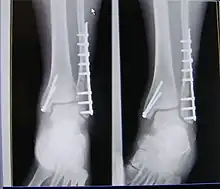

| X-ray of trimalleolar fracture repair before and after ORIF surgery | |

Surgical repair using open reduction and internal fixation is generally required, and because there is no lateral restraint of the foot, the ankle cannot bear any weight while the bone knits. This typically takes six weeks in an otherwise healthy person, but can take as much as twelve weeks. Non-surgical treatment may sometimes be considered in cases where the patient has significant health problems or where the risk of surgery may be too great.[2]